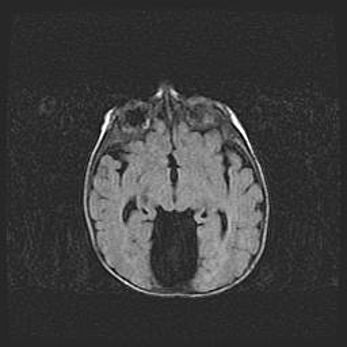

Лейкомаляция с кистозно-глиозной дегенерацией головного мозга.

Возраст: 2 месяца 25 дней

Вес: 6400 г

Окружность головы: 40 см

Срок гестации: 41 неделя

Лейкомаляцию относят к ишемически-гипоксическим повреждениям головного мозга, диагностируемым у новорожденных. При лейкомаляции в головном мозге обнаруживают очаги некроза, возникшие после тяжелой гипоксии и нарушения кровотока. В процессе морфогенеза очаги проходят три стадии: 1) развития некроза, 2) резорбции и 3) формирования глиозного рубца или кисты. Перивентрикулярная лейкомаляция (ПЛ) встречается примерно в 12% случаев среди новорожденных, обычно – у недоношенных детей, причем, частота ее зависит от массы, с которой младенец появился на свет. Наибольшее число малышей страдает лейкомаляцией, если масса при рождении 1500-2500 г.